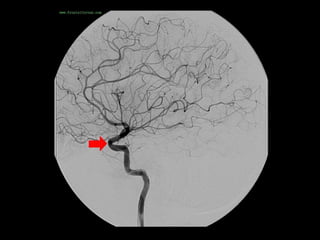

-Anterior temporal branch (best seen in AP view) , a typical

appearance of an anterior temporal branch of the MCA

proximal to the main bifurcation is indicated with the arrow